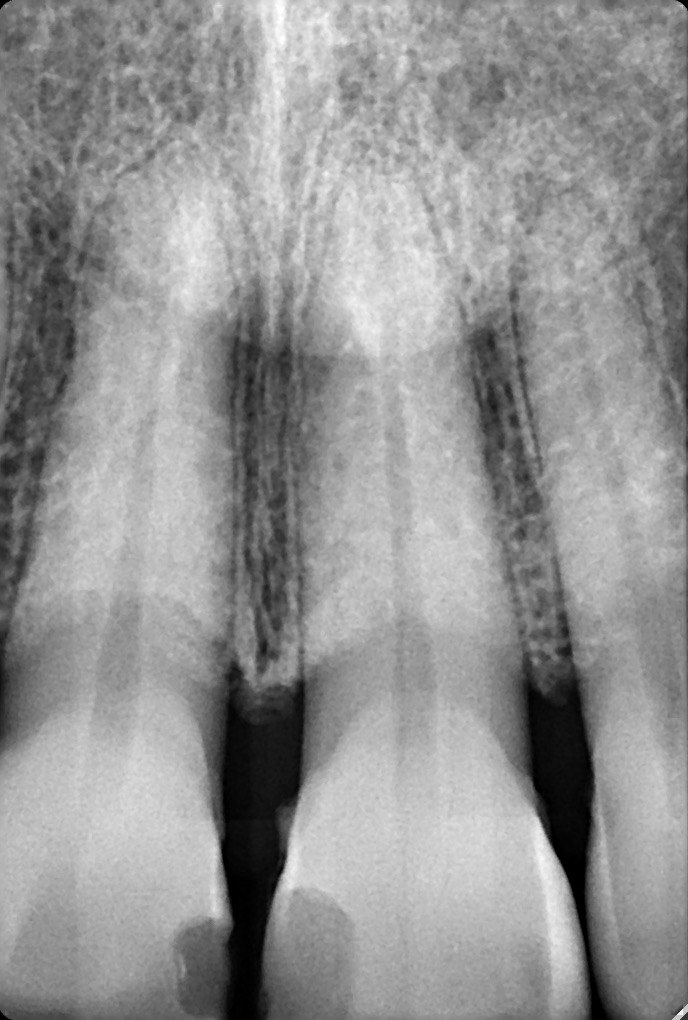

11. What is the radiolucency on the teeth # 1.1, 1.2, 1.3?

14. What condition can be seen on the root surface of tooth # 1.1.?

18. What condition can be seen in buccal surface of the teeth # 1.1 ans 2.1?